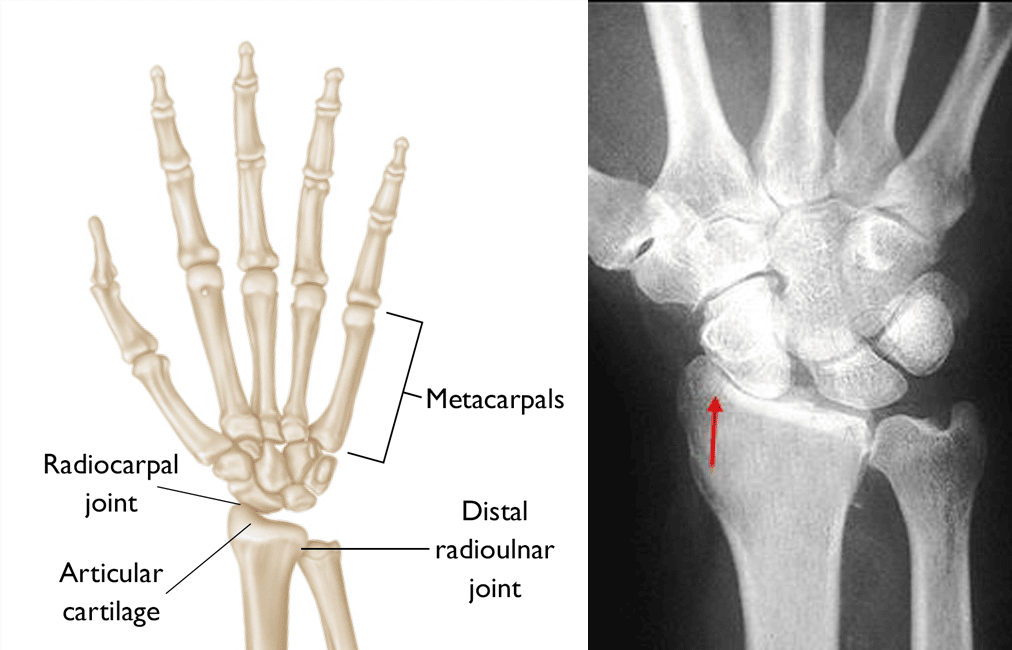

Wrist anatomy and osteoarthritis

(Left) Illustration showing the bones of the wrist and hand. Articular cartilage protects the ends of bones where joints meet. (Right) In this X-ray of a wrist with osteoarthritis, the cartilage is destroyed and the healthy space between bones is narrowed (arrow).

(Left) Reproduced from J Bernstein, ed: Musculoskeletal Medicine. Rosemont, IL, American Academy of Orthopaedic Surgeons, 2003. (Right) Reproduced from JF Sarwark, ed: Essentials of Musculoskeletal Care, ed 4. Rosemont, IL, American Academy of Orthopaedic Surgeons, 2010.

• On the hand side of the wrist, there are two rows of bones that connect the end of the forearm to the hand. These bones are called carpal bones, and there are four of them in each row. There is movement between the carpal bones during wrist motion.

• Past the carpal bones are the metacarpals, which sit on the last row of carpal bones, connecting the wrist to the fingers.

• The radius and ulna are the two bones of the forearm that form a joint with the first row of carpal bones; this joint is important in flexing and extending the wrist. The radius, on the thumb side of the wrist, is wider at the wrist than the ulna and makes up the majority of this joint. The ulna, on the little finger (pinky) side of the wrist, is narrower than the radius at the wrist.

• The joint between the radius and ulna, the distal radioulnar joint, is important in the rotation of the forearm.